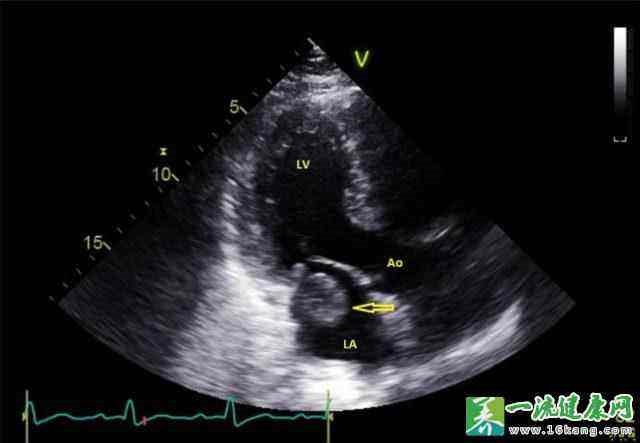

▲ 图6 彩超下左心房血栓